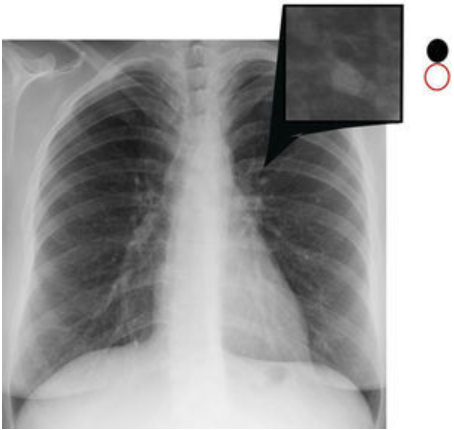

¿Qué signo ves?

**Broncograma aéreo** DATO CLAVE DE CONSOLIDACIÓN ## Footnote (radioopacidad/hiperdensidad con bronquios llenos de aire)